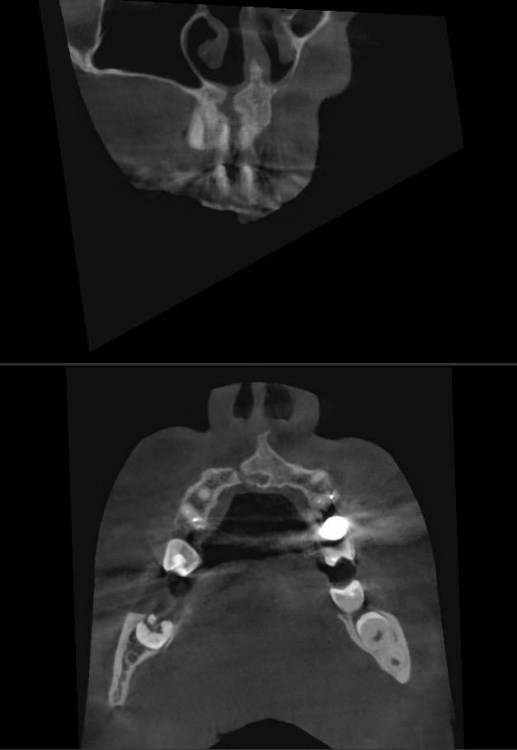

Огромная «киста» во фронте

Кортикалки не было, во второе посещение в каналах удалось добиться сухости

закрыл триоксидеКнтом на случай если понадобится апикалка

На КЛКТ прослеживается ороназальное  сообщение (его и на прицелках видно). Пациента ничего не беспокоит, функция и эстетика восстановлены